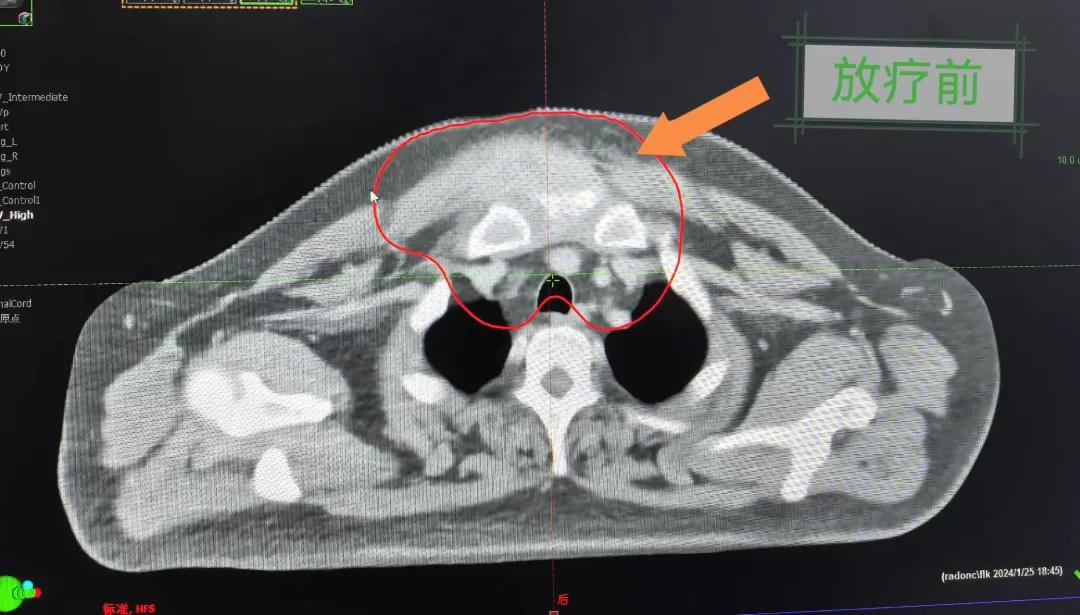

2個(gè)月前,市二院放療科接診了一名特殊的病人。一位40歲的中年男人,其前胸部竟然長了一個(gè)巨大的大腫塊,已有8cm左右且疼痛。

經(jīng)過詳細(xì)詢問病史,得知患者半年前前胸部突然出現(xiàn)一個(gè)腫塊,最初并未引起重視,以為只是普通囊腫,就隨便抹點(diǎn)藥,貼了膏藥。然而,腫塊并未縮小,反而逐漸增大,并伴隨著難以忍受的疼痛,嚴(yán)重影響了患者的日常生活和工作。隨后就診于當(dāng)?shù)蒯t(yī)院,行“胸部腫物穿刺活檢術(shù)”,術(shù)后病理提示為鱗狀細(xì)胞癌。突如其來的打擊讓患者不知所措,盡管嘗試了保守治療,但效果并不理想,僅能暫時(shí)緩解疼痛。

患者經(jīng)多方咨詢與打聽,在家屬的陪同下來到市二院放療科找到趙亮主任尋求幫助。入院后迅速完善了相關(guān)檢查,診斷為罕見的“胸壁腫瘤”。因腫瘤體積大,侵犯周圍組織,手術(shù)治療難度較大,經(jīng)院內(nèi)多學(xué)科會(huì)診后,決定采用無創(chuàng)的局部放射治療。在初步告知患者及家屬治療方案時(shí),病人及家屬都擔(dān)心預(yù)后及放療可能引起的不適,趙亮主任詳細(xì)且耐心的向家屬和病人講述放療過程中可能出現(xiàn)的不良反應(yīng),確保讓他們安心治療。

隨后,趙亮主任帶領(lǐng)放療團(tuán)隊(duì)以最快的速度完成了患者的放射治療計(jì)劃,在保證放療精準(zhǔn)打擊腫瘤的同時(shí),利用先進(jìn)的三維立體精確放療技術(shù),最大限度的避免心臟、肺部的損傷發(fā)生,整體治療精準(zhǔn)度達(dá)到1mm以內(nèi)。經(jīng)過10次的放射治療后,患者疼痛已明顯減輕,胸部腫物肉眼可見的縮小,患者及家屬臉上終于露出久違的笑臉。

治療期間,患者沒有出現(xiàn)明顯不適,治療結(jié)束后,患者胸壁腫物由最初8cm縮小至約1cm,后患者至外科行手術(shù)治療。